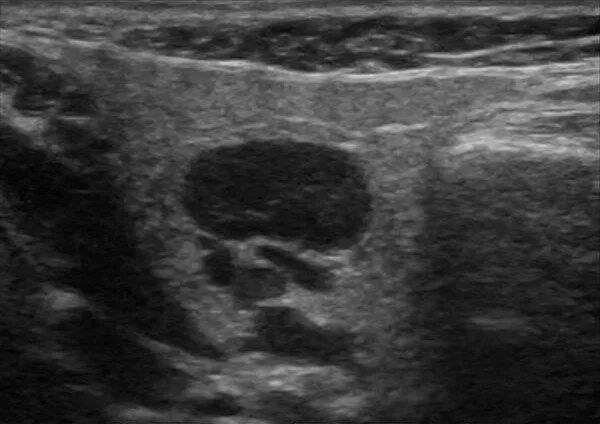

Метастазы в паховых лимфоузлах